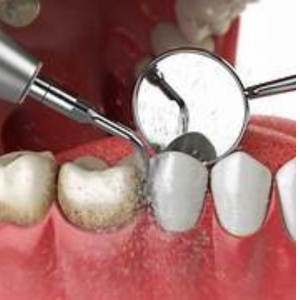

Our tooth scaling and teeth cleaning service is designed to remove plaque, tartar, and surface stains to keep your teeth and gums healthy. Using modern ultrasonic tools and gentle techniques, we provide a refreshing, comfortable, and highly effective dental cleaning experience.

We use advanced ultrasonic scalers that gently break down plaque and bacteria for a safe and comfortable cleaning.

Removal of plaque and tartar using ultrasonic instruments.